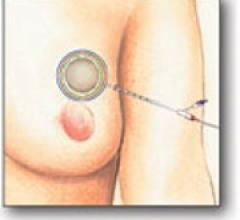

October 19, 2011 — Hologic Inc. announced the six-year follow-up results from the MammoSite Registry Study continue to show promising results for breast cancer patients. The results were presented at the American Society of Radiation Oncology (ASTRO) meeting in Miami, Florida, Oct. 3. The company featured its next-generation MammoSite ML (multi-lumen) radiation therapy.

At RSNA 2011, Hologic will showcase its new Trident specimen radiography system, which uses proprietary direct digital detector technology. The imaging system produces high quality images for rapid verification of tissue specimens such as breast biopsy samples.